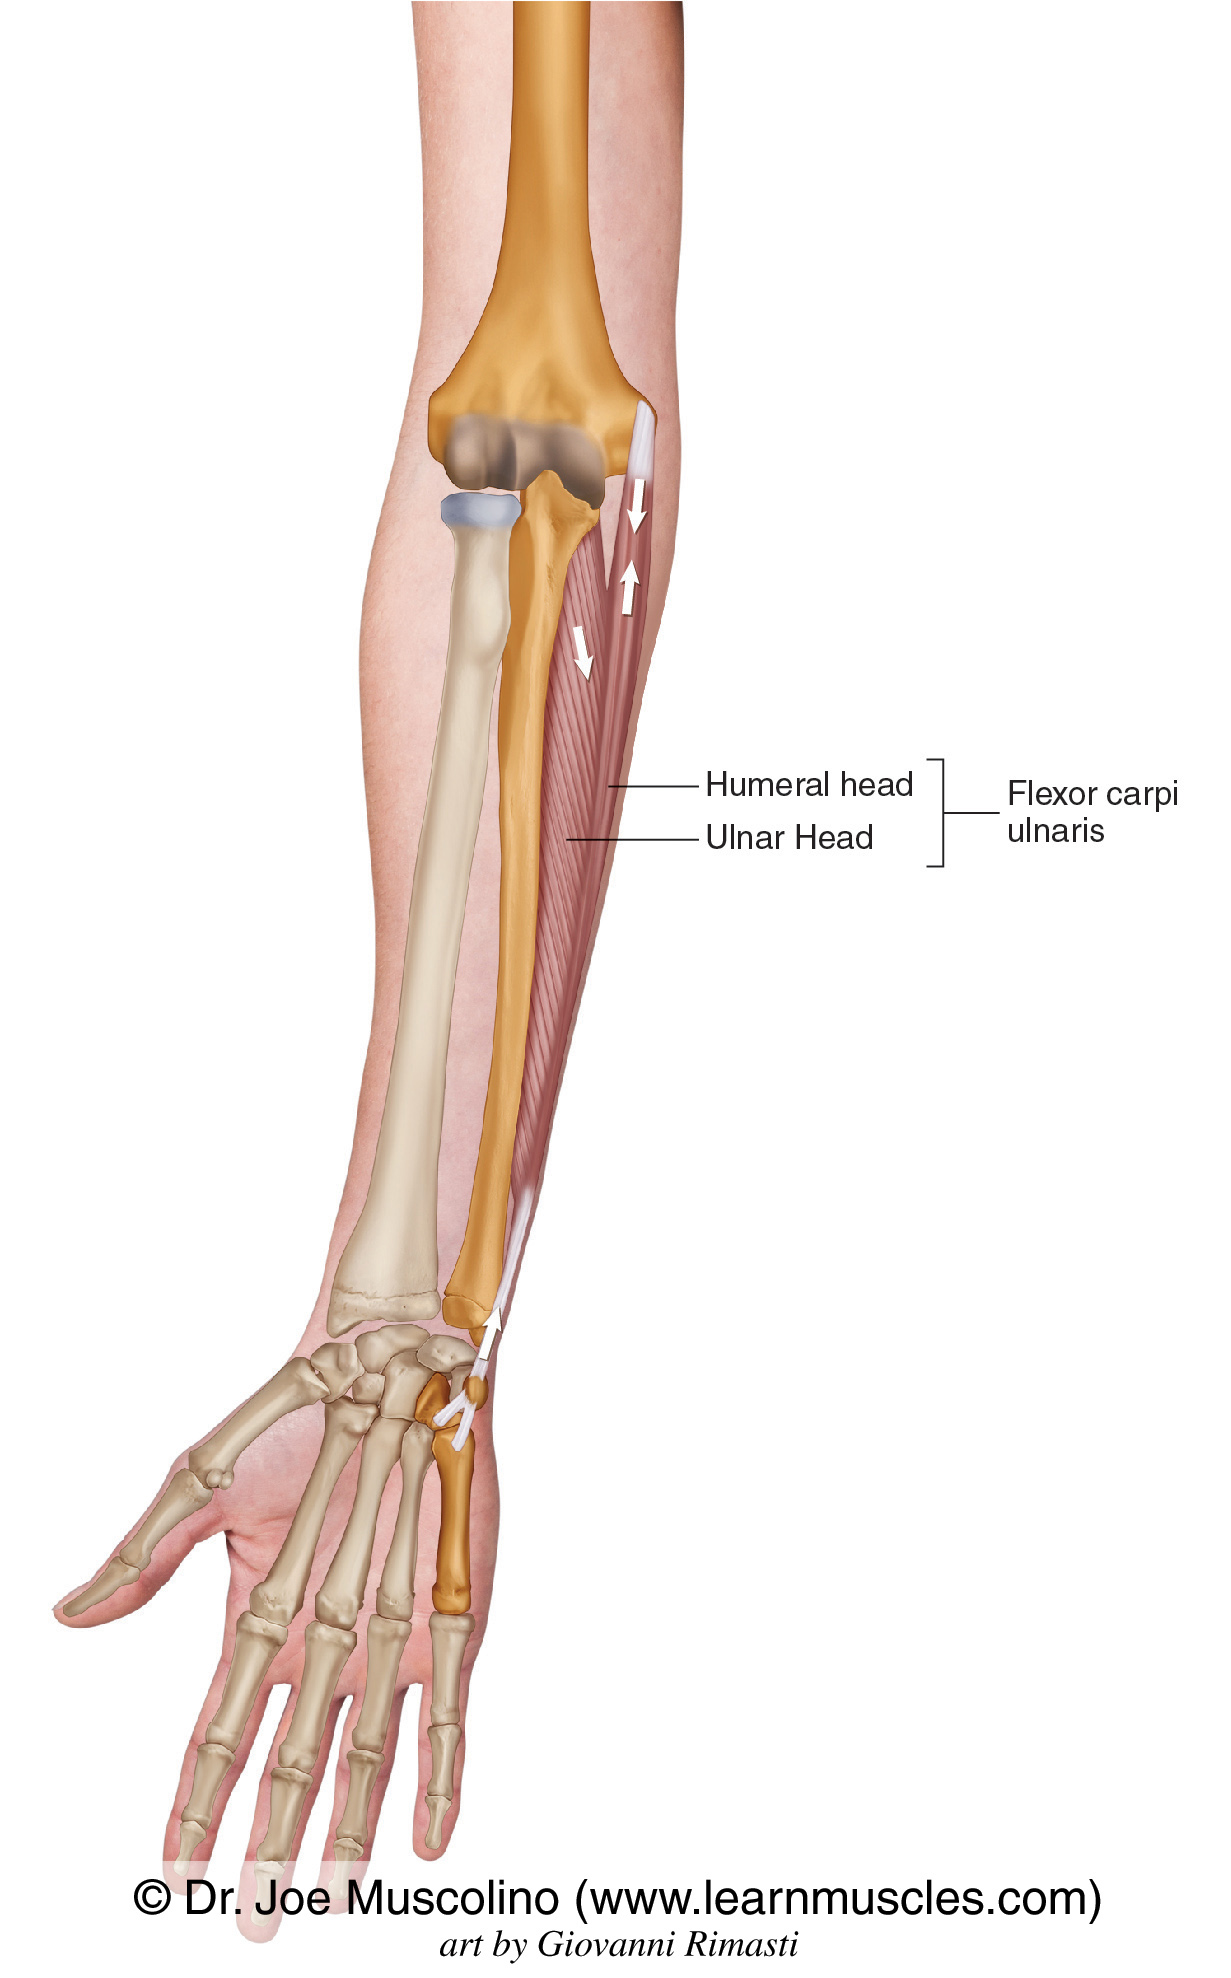

Анатомия мышцы Palmaris Longus